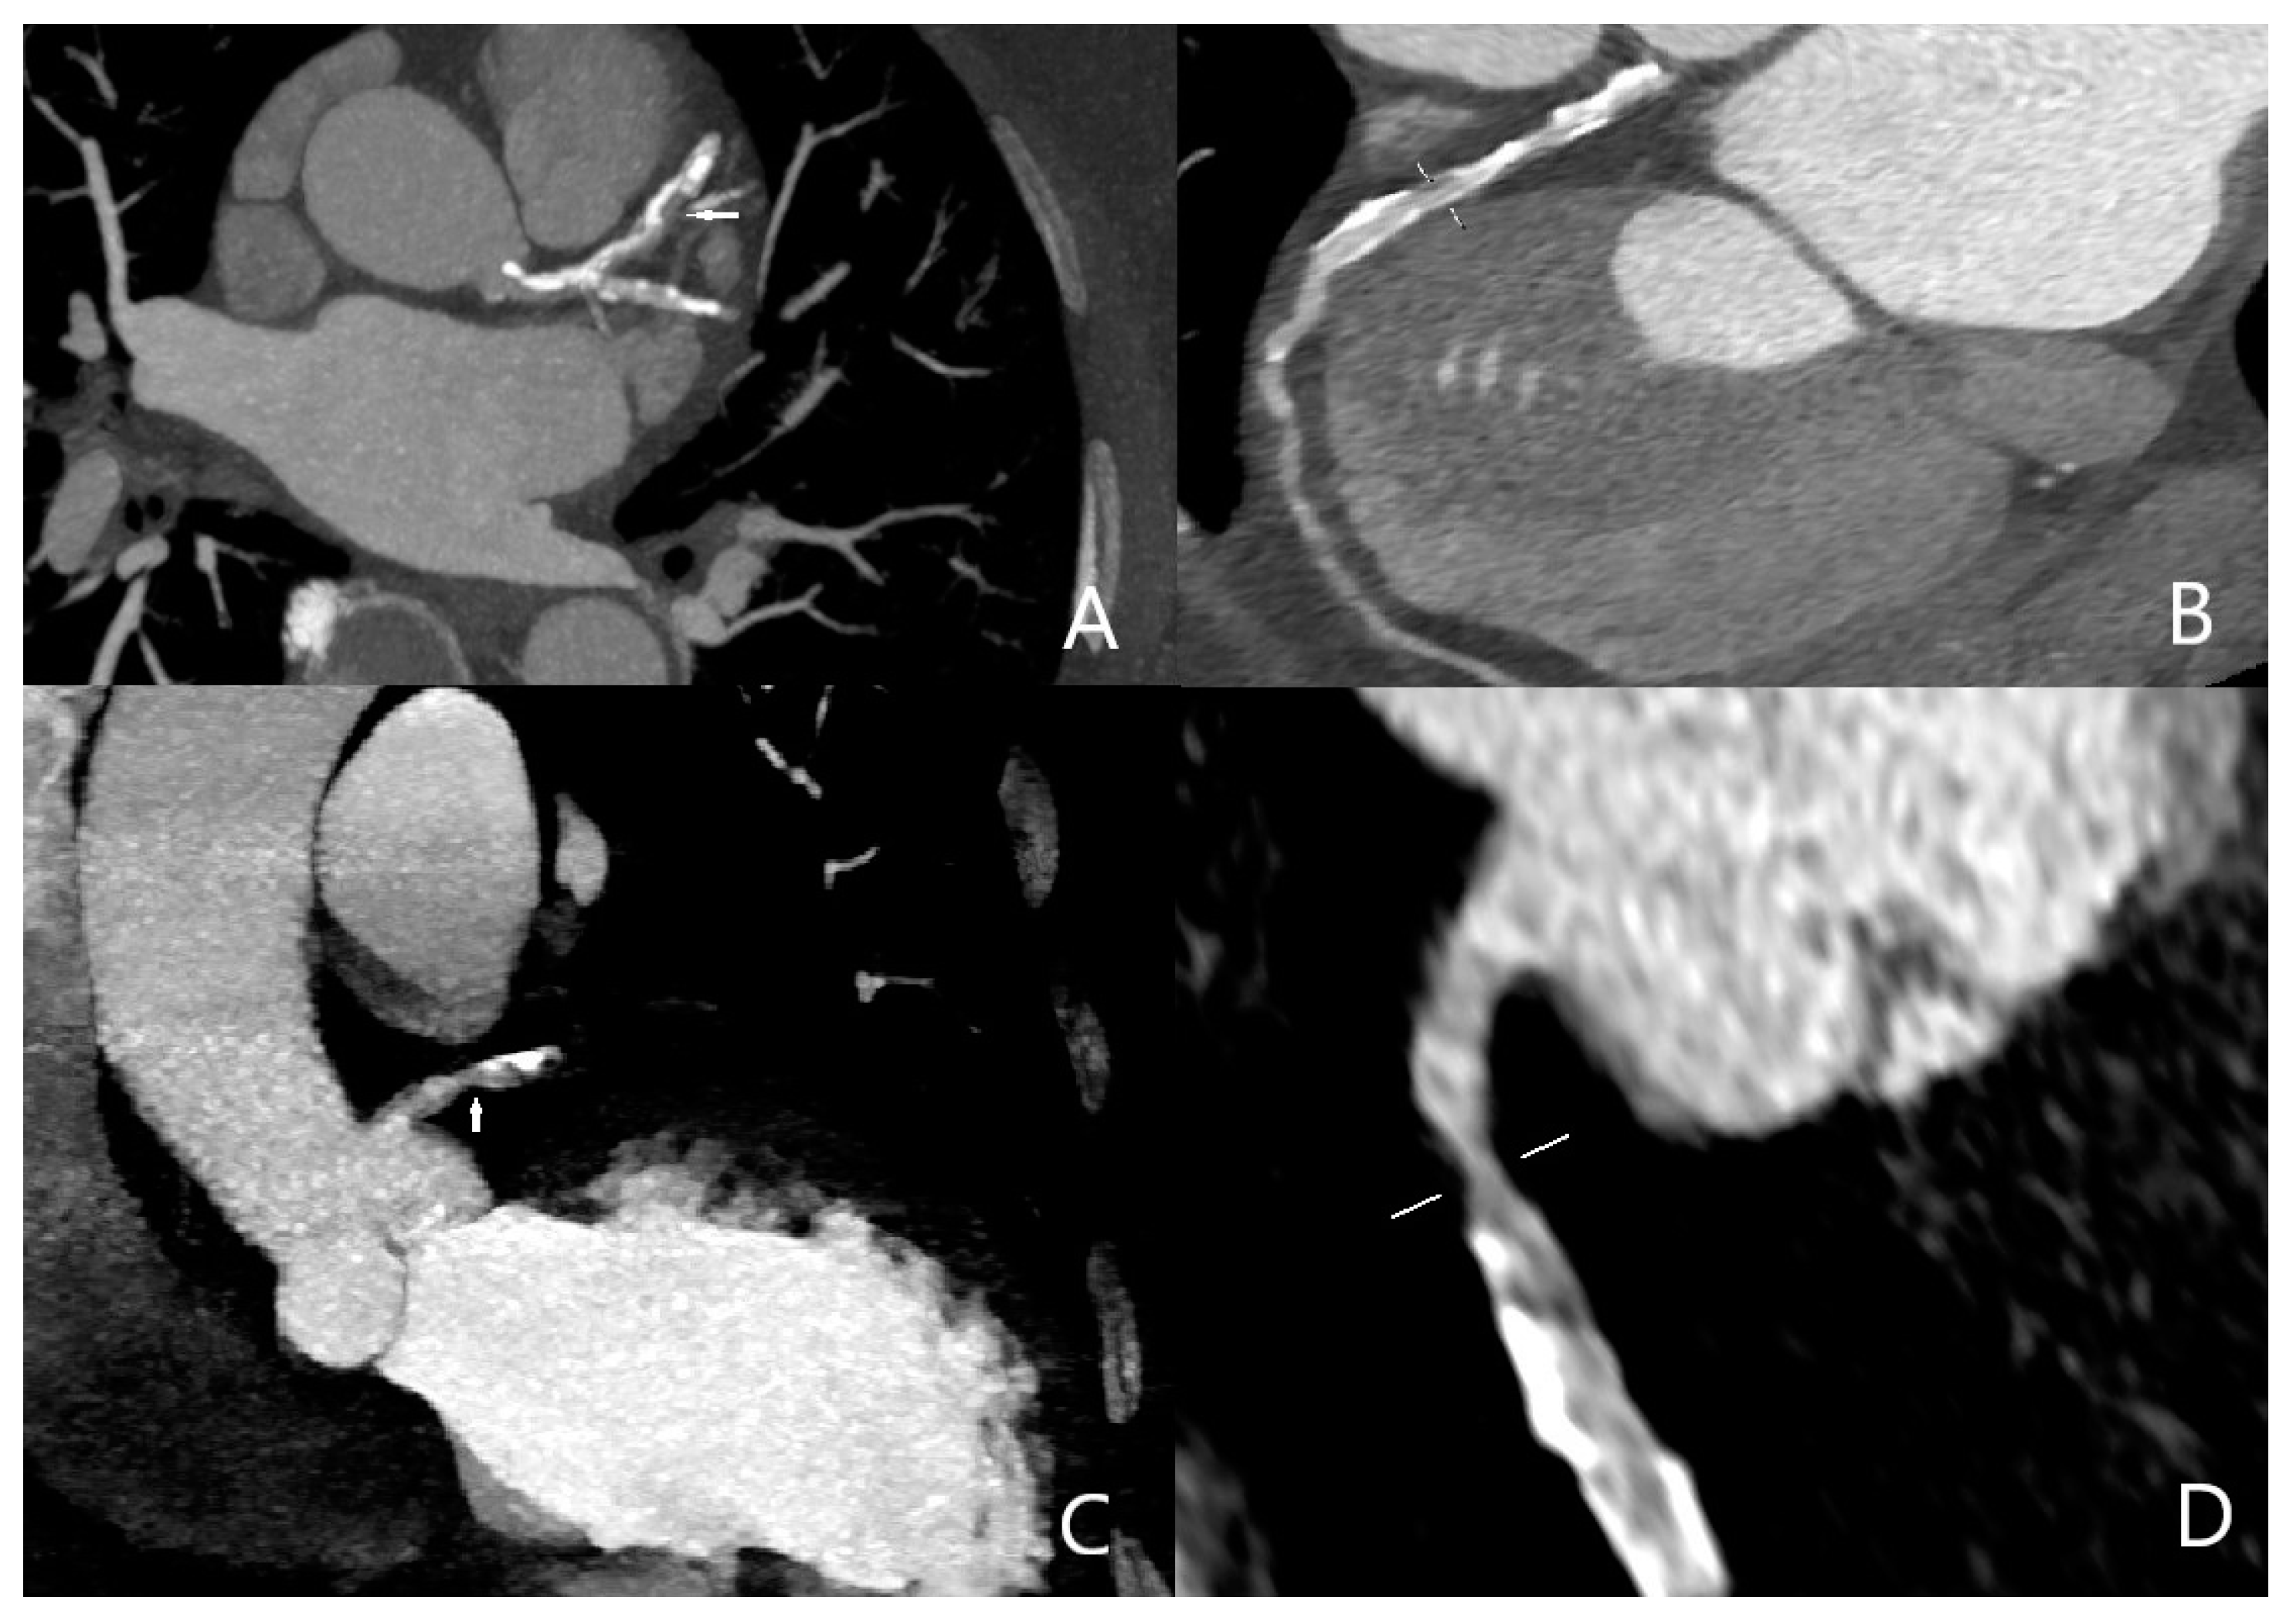

Two cases of distal pulmonary embolism could not be diagnosed with CT scan, and no false positive results were detected (Figure 1). Sensitivity, specificity, and positive and negative predictive values of quadruple-rule-out CT for pulmonary embolism were 93.5% (95% confidence interval [CI] 90–100%), 100% (95%CI 96–100%), 100% (95%CI 97–99%), and 95.3% (95%CI 93–100%), respectively. Cohen’s coefficient of variation (ĸ value) for the presence of pulmonary embolism was 0.95 (almost perfect).

Figure 1.

Filling defects (arrows) on pulmonary arterial phase in the both main and left upper lobar pulmonary artery consistent with pulmonary embolus. ((A) axial; (B) coronal).